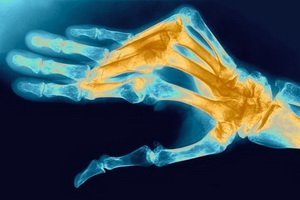

Дискомфорт при синдроме может проявляться в состоянии покоя. Наблюдается частое сокращение мышц. На повреждённой руке ногти будут хрупкими. Если пациенту сделают рентгеновский снимок, то будет видно снижение плотности костной ткани.

Синдром Зудека – это состояние организма, характеризующееся болью неврологического характера в верхних или нижних конечностях, а также нарушением трофики, тонуса сосудов, кровообращения и развитием остеопороза костей.